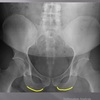

AP LUMBOPELVIC LANDMARKS A-P lumbopelvic view

femur heads

110

A-P lumbopelvic view

superior iliac crests

111

lateral iliac crests

112

ischial tuberosities

113

s2 tubercle

114

pubic/pubic symphysis

115

sacral grooves

116

lateral aspect of sacrum

117

medial aspect of ilium

118

obturator foramen

119

spinous processes

120

supeiror endplate tips

121

lumbar pedicle shadow